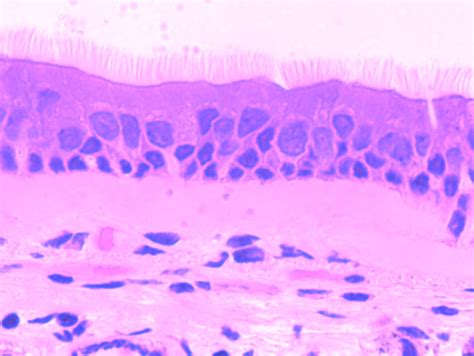

Pseudostratified Ciliated Columnar / / The cells that comprise the epithelial membranes are variously shaped and are named accordingly.. Includes secretory, nonciliated cells (with basal nuclei). Its function is to protect these trachea composes of pseudostratified columnar, ciliated epithelium, goblet cells. Pseudostratified ciliated columnar epithelium consists of a single layer of cells. A pseudostratified columnar epithelium is a tissue formed by a single layer of cells that give the appearance of being made from multiple layers, especially when seen in cross section. Find out information about pseudostratified ciliated columnar epithelium.

Epithelial tissue lines the inner and outer surfaces of organs in the body and function in processes of secretion, absorption. A type of epithelium in which all cells reach to the basement membrane but some extend toward the surface only part way. The pseudostratified columnar epithelium is found in different parts of the body and each specific location serves different functions. The cells that comprise the epithelial membranes are variously shaped and are named accordingly. Ciliated pseudostratified columnar epithelia is found lining the trachea and upper respiratory tract.

Ciliated pseudostratified columnar epithelia is the type of respiratory epithelium found in the linings of the trachea as well as the upper respiratory tract. Pseudostratified ciliated columnar epithelium consists of a single layer of cells. Epithelial tissue lines the inner and outer surfaces of organs in the body and function in processes of secretion, absorption. Learn about pseudostratified ciliated columnar epithelium with free interactive flashcards. Pseudostratified ciliated epithelium lines the nasal cavities, trachea, and bronchi. Posteriorly, the epithelium is a pseudostratified ciliated columnar epithelium that covers the respiratory regions (formed by the maxilloturbinates).45,107,110 the superior turbinate. As it rarely occurs as squamous or cuboidal epithelia. Cliffsnotes states that the pseudostratified characterization comes from the fact that ciliated columnar epithelium cells appear to have multiple layers when there is actually just one cell.

This gives the appearance of multiple layers. Epithelial tissue lines the inner and outer surfaces of organs in the body and function in processes of secretion, absorption. 200 to 300 cilia per cell; Lines the nasal cavities, trachea, and bronchi by secreting mucus by goblet cells and move mucus with cilia. + pseudostratified columnar epithelial tissue. Histology of trachea histology slide of trachea histological slide of trachea. Pseudostratified ciliated columnar epithelium video. A pseudostratified epithelium is a type of epithelium that, though comprising only a single layer of cells, has its cell nuclei positioned in a manner suggestive of stratified epithelia. The cells that comprise the epithelial membranes are variously shaped and are named accordingly. The respiratory airways are lined by a pseudostratified columnar epithelium with a variety of distinct cell types including. As it rarely occurs as squamous or cuboidal epithelia. Crogvpseudostratified columnar tumor cells present. Ciliated pseudostratified columnar epithelia is the type of respiratory epithelium found in the linings of the trachea as well as the upper respiratory tract.

Unlike simple columnar epithelium, the nuclei are arranged at different levels within the cells. Pseudostratified ciliated epithelium lines the nasal cavities, trachea, and bronchi. Histology of trachea histology slide of trachea histological slide of trachea. Pseudostratified ciliated columnar epithelium cells function as a protective layer in the respiratory system of humans. Note the ciliated, pseudostratified columnar epithelium lining the tracheal lumen.

The pseudostratified columnar epithelium is found in different parts of the body and each specific location serves different functions. The trachea is lined with ciliated pseudostratified columnar epithelium. In some columnar epithelia, the cells become so crowded that some of the nuclei become displaced and several rows of nuclei appear in sections of the cell sheet. Pseudostratified ciliated epithelium lines the nasal cavities, trachea, and bronchi. A pseudostratified columnar epithelium is a tissue formed by a single layer of cells that give the appearance of being made from multiple layers, especially when seen in cross section.

Pseudostratified ciliated columnar epithelium consists of a single layer of cells. A pseudostratified columnar epithelium is a tissue formed by a single layer of cells that give the appearance of being made from multiple layers, especially when seen in cross section. Pseudostratified columnar epithelia are found forming the straight, tubular. A pseudostratified epithelium is a type of epithelium that, though comprising only a single layer of cells, has its cell nuclei positioned in a manner suggestive of stratified epithelia. Ciliated pseudostratified columnar epithelia is the type of respiratory epithelium found in the linings of the trachea as well as the upper respiratory tract. Histology of trachea histology slide of trachea histological slide of trachea. A type of epithelium in which all cells reach to the basement membrane but some extend toward the surface only part way. As it rarely occurs as squamous or cuboidal epithelia. The cells that comprise the epithelial membranes are variously shaped and are named accordingly. The trachea is lined with ciliated pseudostratified columnar epithelium. Ciliated pseudostratified columnar epithelia is the type of respiratory epithelium found in the linings of the trachea as well as the upper respiratory tract. It is said to be pseudostratified (pseudo = false) because its structure creates a visual illusion of being multilayered. Pseudostratified ciliated columnar epithelium cells function as a protective layer in the respiratory system of humans.